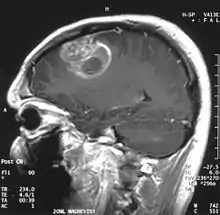

| Coronal MRI with contrast of a glioblastoma in a 15-year-old male | |